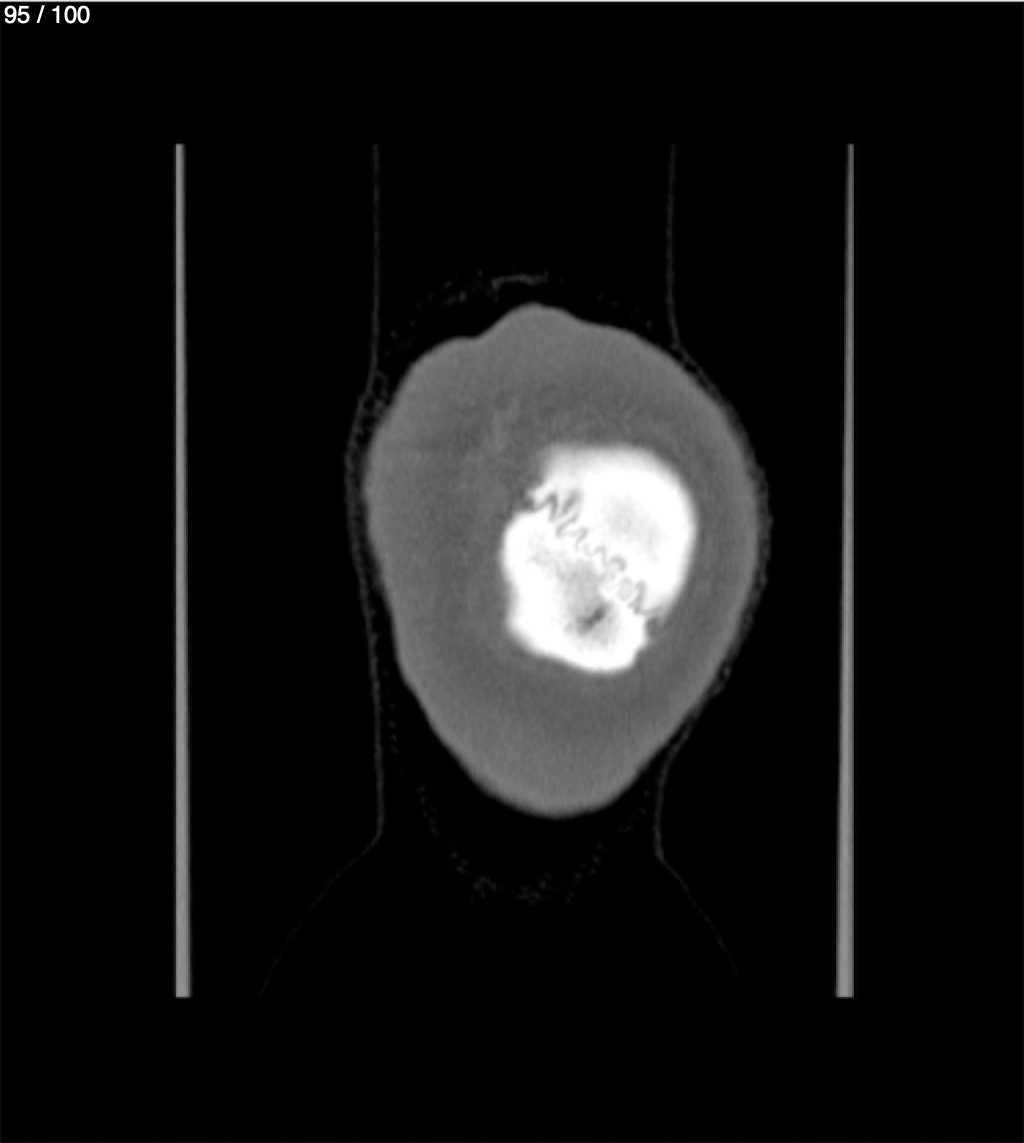

Yonelly Barrios Diaz 35A - T.C Craneo